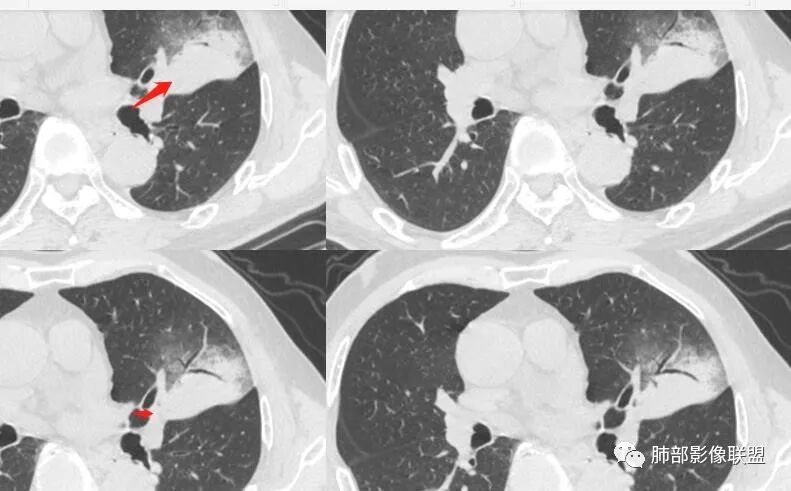

支气管?

宇宙星空:

堵塞

尘缘:

支气管外面堵了,近端有扩张

有堵塞,有狭窄

南边:

中远端堵塞,堵塞端圆钝

炎性? 肺炎型肺癌待排

血管受侵了吧

空洞内侧软组织肿块,比较支持恶性吧

这个空洞的性质很重要,对最后诊断结果影响大,如果中间没有曲菌球,那就是偏心空洞,指向恶性,如果是曲菌球引起的新月形改变,那就不一定。至于到底是曲菌球还是偏心空洞,需要仔细看看强化情况。

不均匀性强化,远端坏死比较明显